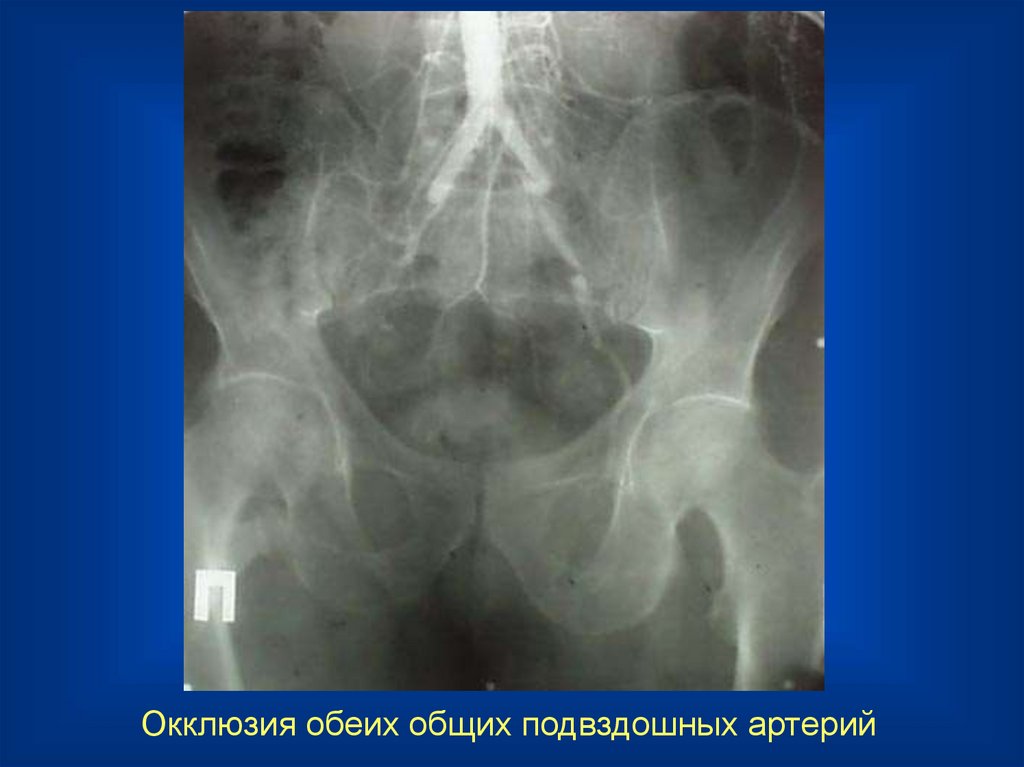

10.

Окклюзия левой общей подвздошной артерии

11.

Состояние после подвздошно-подвздошного шунтирования справа

12.

Окклюзия обеих общих подвздошных артерий